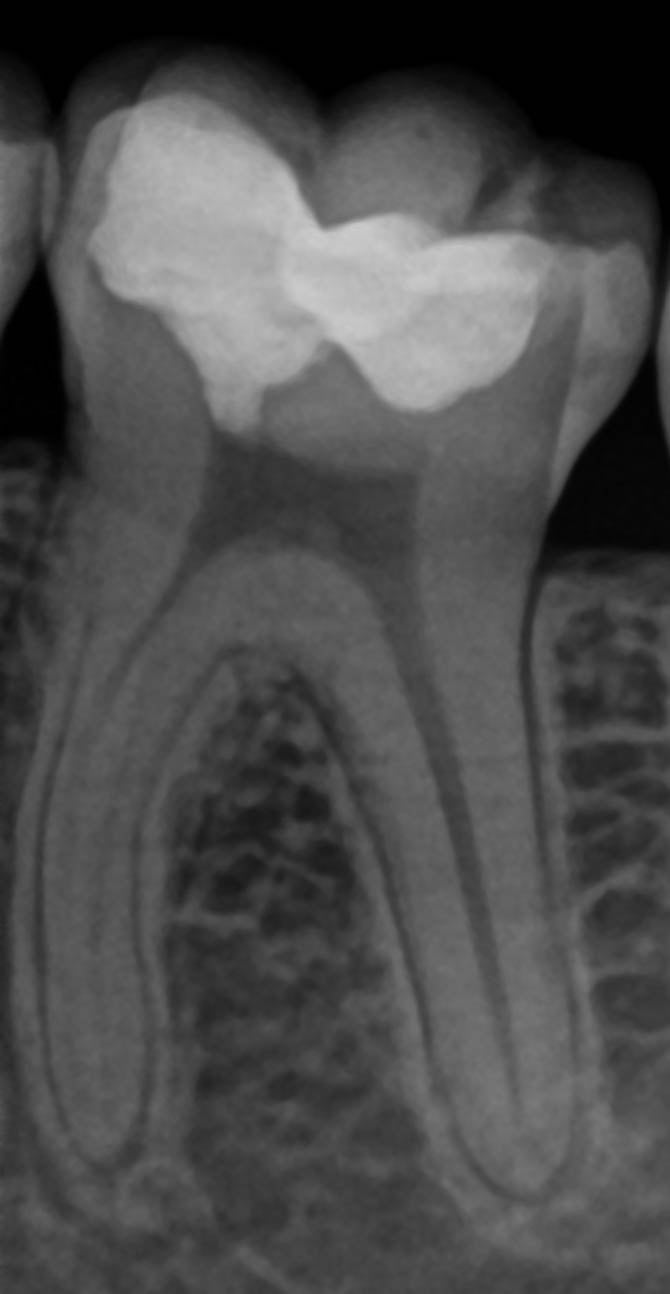

The patient was initially seen in a general dental practice, where deep secondary caries located very close to the pulp of a lower left molar were identified. As preserving pulp vitality was the top priority, the patient was referred directly to Georg Benjamin’s specialised endodontic practice.

Following examination, Benjamin diagnosed symptomatic reversible pulpitis and began by performing a cold test to determine whether the pulp was still fully vital. As the response was positive, he opted for a partial pulpotomy to remove the deep caries and maintain the nerve’s vitality.

The stages of a partial pulpotomy in pictures

Digital volume tomography (DVT) and clinical photographs taken 12 months after treatment show a stable condition of tooth 36 following partial pulpotomy. Sensitivity testing, percussion testing, and circular probing of the surrounding gingiva confirm that both pulp vitality and periodontal health were successfully maintained thanks to Komet BioRepair.